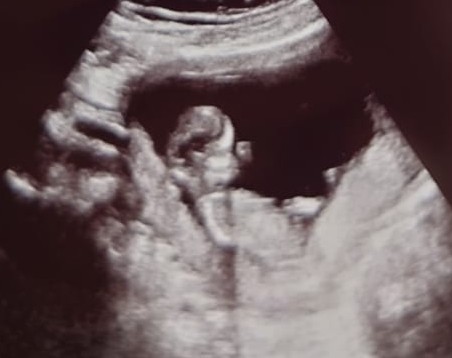

PumpkinEverything · 31/03/2021 19:10

Oh and here’s one of my photos 😊 they were wriggling a lot so not a really clear photo but so happy as she literally gave us like 20! She said it’s not her that pays for them 😂 even have one where you can see their hand which was lovely. She was so so nice today

We got there in the end. Baby measuring 11+5 with EDD of 15th Oct. That's exactly right based on my LMP. Here is a scan photo of baby not co-operating by sitting up. After lots of walking and jumping around, and then lots of prodding from the sonographer, we got baby to lie down for the measurements. I didn't mind it taking longer, as we got to see the baby dancing away and wriggling for ages.

Lovely photo @PumpkinEverything. I think it's quite clear considering all the wriggling.